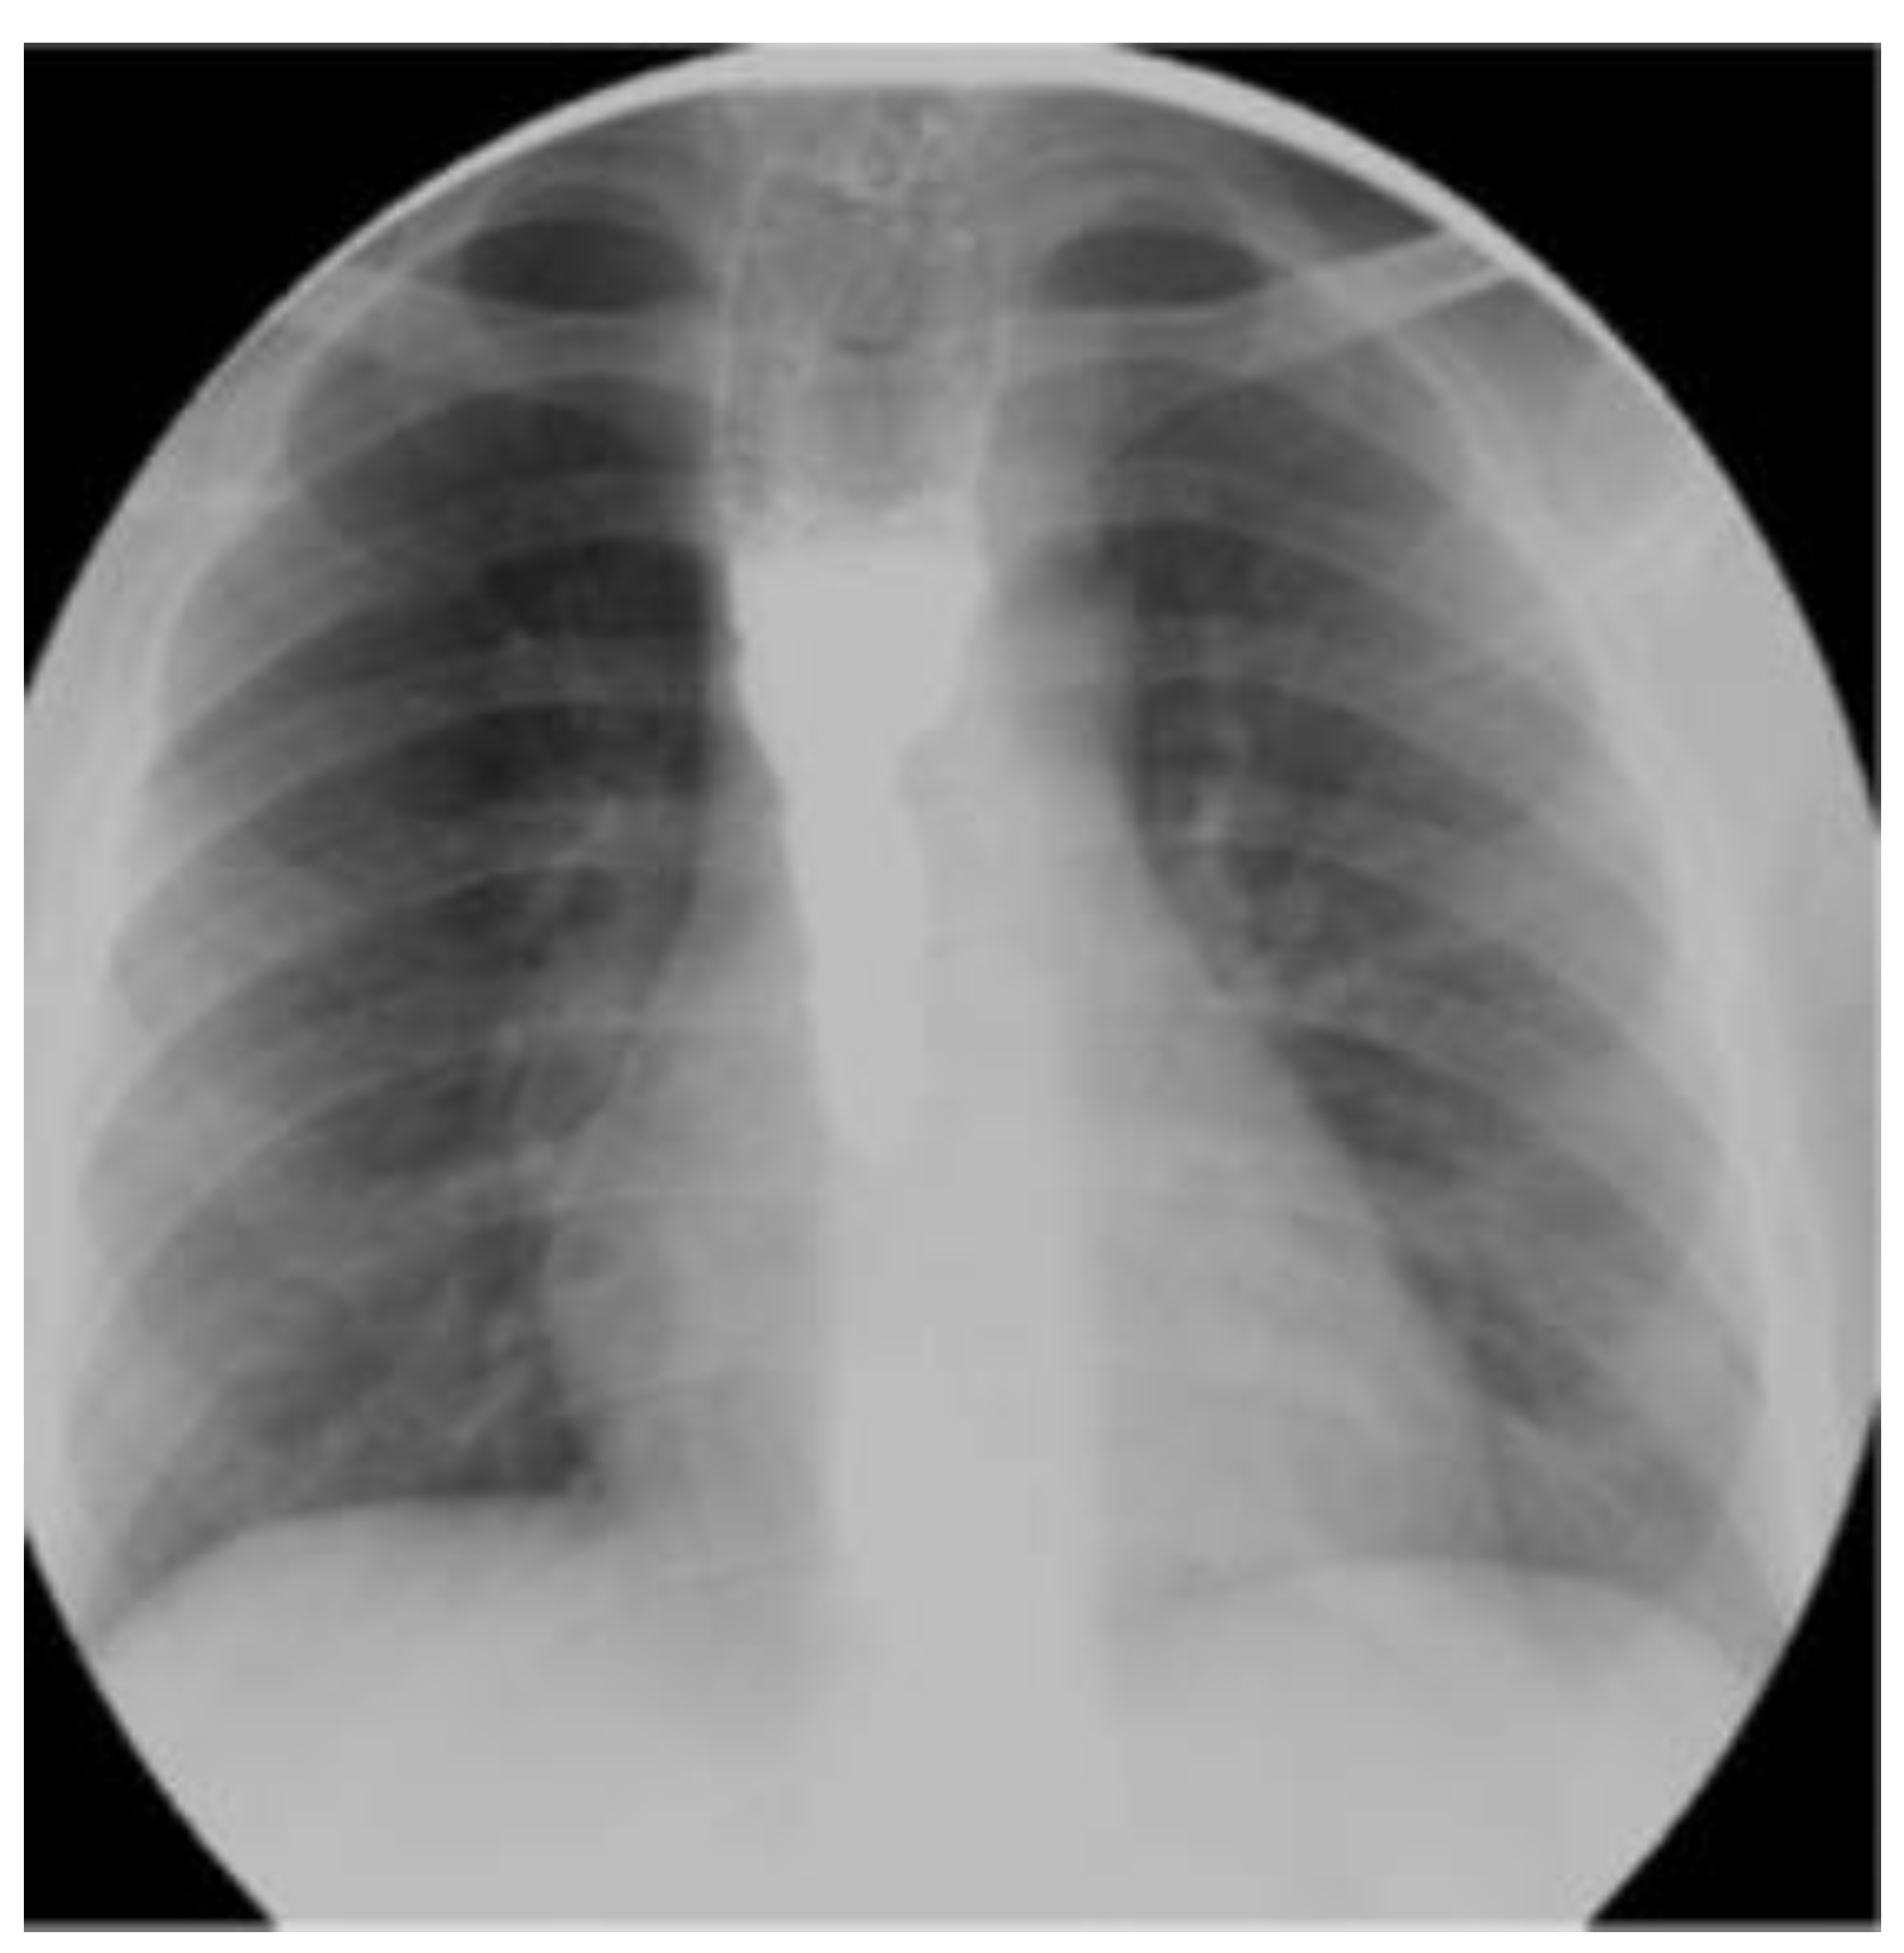

Case Report